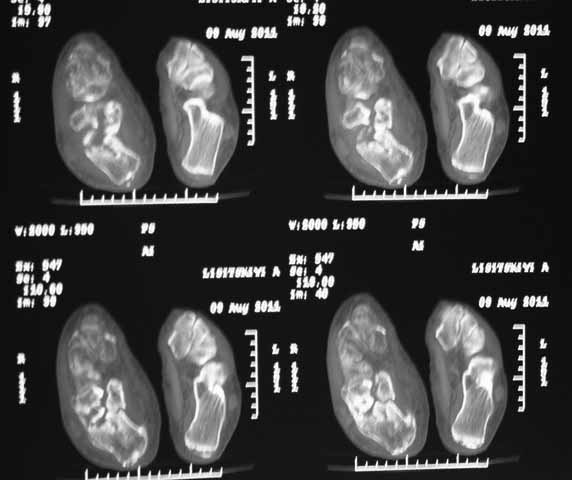

КТ перелома пяточной кости Пациент 60 лет с производственной травмой-закрытые переломы правой пяточной кости, тибиального плато слева поступил в феврале с.г. На 4 сутки выполнена открытая репозиция, остеосинтез внутрисуставного перелома голени, ручная репозиция пяточной кости. Через три месяца начал ходить с нагрузкой на обе ноги. Консолидация голени с полным восстановлением функции колена. Правая стопа умеренно отечна, продольно распластана, длительная ходьба вызывает боли и увеличение отека. Прошел несколько курсов ударно-волновой терапии, грязелечение, боли и отек уменьшились. В наших планах -оформление на ВТЭК, через год возможно выполнение подтаранного артродеза.Но после производства КТ в августе появились сомнения в консолидации перелома.Ранее у нас не было опыта КТ переломов стопы и сканы привели в замешательство.Прилагаю снимки со дня поступления, августовские пациентом не представлены.С благодарностью примем советы коллег.

Данное исследование сделано в неправильной позиции стопы, стопа находится под прямым углом. Но несмотря на это, здесь можно увидеть, что латеральная стенка смещена, фиброз между фрагментами и варусное смещение пятки.

Топография зависит от позиции пятки в пространстве и неправильное положение закрывает обзор нужных структур. Важными структурами в исследовании пятки является задняя фасетка, бугор и боковые стенки. Существует специальные рентгенснимки, показывающие импинджмент с лодыжкой, а также положение бугра. Для КТ стопу надо инклинировать под 30 градусов, иначе можно пропустить важные переломы.